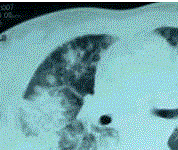

问题 患者女,23岁。间断发热伴皮疹1年半,诊断红斑狼疮。长期间断应用糖皮质激素治疗。近20 d来高热(T 39℃)伴咳嗽咳痰, CT(附图)示双肺满布圆形密度增高阴影,大小不等,密度不均匀,上、中肺野分布较多,双侧少量胸腔积液。血常规:WBC 2.52×10/L, N 0.62, Hb 92 g/L;ESR 40 mm/h;痰真菌培养:烟曲霉3次阳性;支气管镜检查右下叶、左舌段见黄色黏液性血性分泌物,毛刷找到霉菌孢子。 本病例诊断属于

选项 A.确诊(proven) B.临床诊断(probable) C.拟诊(possible) D.定植(colonization) E.不能确诊

答案 B